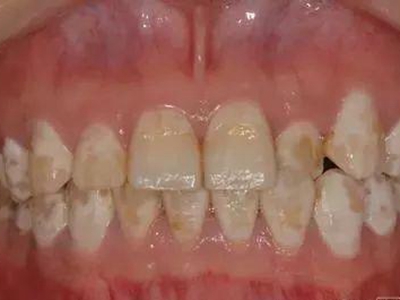

牙釉质发育不全牙齿白斑图

牙釉质发育不全患者可以仅仅出现牙齿色泽和透明度的改变,形成白垩色釉质,即类似于牙齿上有白斑,此时牙冠形态通常较完整。

牙釉质发育不全牙齿上出现白色的斑块图

牙釉质发育不全患者牙釉质表面出现白垩色釉质,表现为牙齿表面色泽不均匀,一般无自觉症状,并且此时牙冠形态较为完整,顶端出现小的缺损。